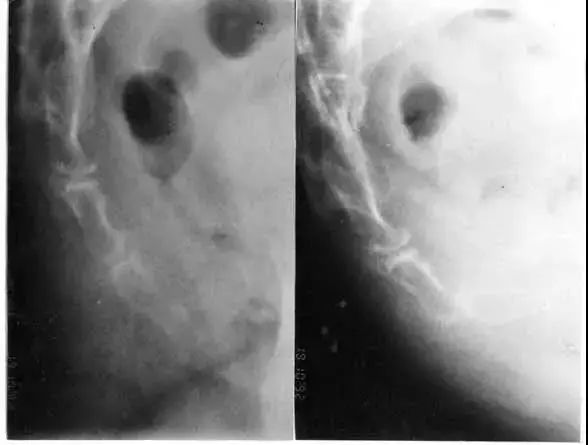

X 光片是评估尾骨位置与活动度最常用的工具:(要拍站立与坐姿来比较)。

在侧面的X光片中(站姿+坐姿)有几种状况是我们可能看到的:

1向后脱位(Posterior luxation and subluxation)

若是向后位移超过尾骨前后径的25%就称为尾骨脱位了。这是比较常遇到的,患者在坐着的时候,荐骨尾骨或是第一第二尾骨间关节发生向后脱位的现象,但是大部分的人在站立时又自动归位了。

因为一般的X光拍摄都是站着或是躺着照,所以向后脱位常会被忽略掉。这类的患者有比较胖、跌坐病史的趋势,而且在由坐到站的过程中,通常会觉得比单纯坐着来的痛。

2向前活动度过大(Hypermobility in flexion)

我们比较站着与坐姿时,尾骨向前旋转的角度若是超过25度就称为活动度过大。

图A是站立照。图B是已经坐下来的片子。

图C是将图A摆在图B上,并且使荐骨重叠,角度i即为所求。

如果入射角>35度,则坐下来时尾骨偏向于向后跑;假如<12度,则偏向向前跑。